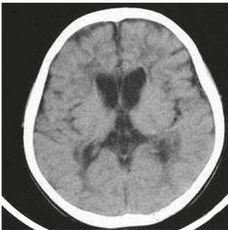

C) Brain Scans: These help doctors understand what kind of brain damage may have occurred.